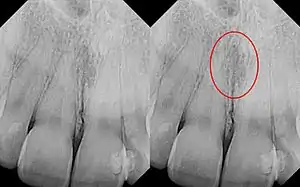

| Identical images with heart-shaped radiolucency highlighted in right film. | |

As a cyst, the nasopalatine duct cyst requires histological analysis for a definitive diagnosis. Radiographically, the nasopalatine cyst appears as a well-demarcated round, ovoid, or heart-shaped structure presenting in the midline of the maxilla.[6]